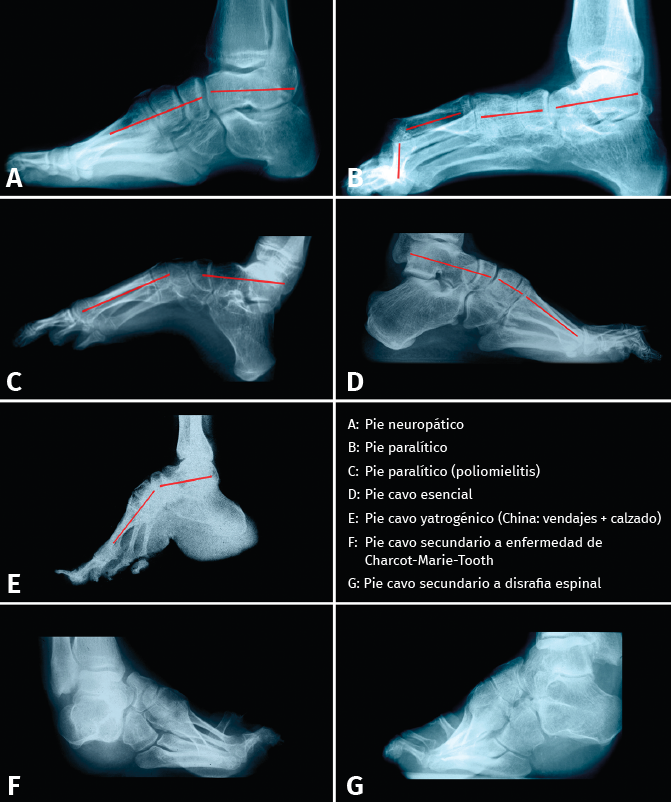

Las alteraciones tridimensionales en el pie cavo son muy variables, lo que condiciona formas clínicas muy diversas. No tiene nada que ver, ni desde un punto de vista clínico ni radiológico, el aspecto de un pie cavo hipertónico de un deportista con el que presenta un pie neurológico con marcado varo de talón, o un pie cavo secundario a una secuela de poliomielitis o a una enfermedad de Charcot-Marie-Tooth. Por ello, es muy difícil asegurar que existe o no una alteración en la forma del primer CM la primera cuña o en qué articulación se produce la rotura de la línea de Meary (Figuras 6A y 6B).

Figura 6. Rotura de la línea de Meary en diferentes tipos de pie cavo (A, B, C, D y E), en los que puede observarse una gran variabilidad de la misma. En F y G, debido a la alteración tridimensional, es difícil trazar la línea de Meary.